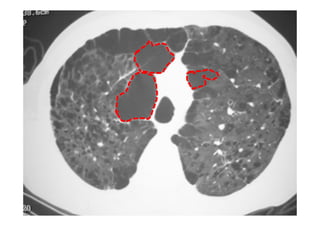

Utiliza-se com frequência p/ avaliar:

Alterações patológicas e diagnóstico de pneumopatias;

Radiografia e TC de tórax

Utiliza-se com frequênciap/ avaliar: O posicionamento do TOT: 4-6 cm acima da carina; Se os pulmões estão sendo aerados adequadamente; Alterações patológicas e diagnóstico de pneumopatias; Outros. Radiografia e TC de tórax